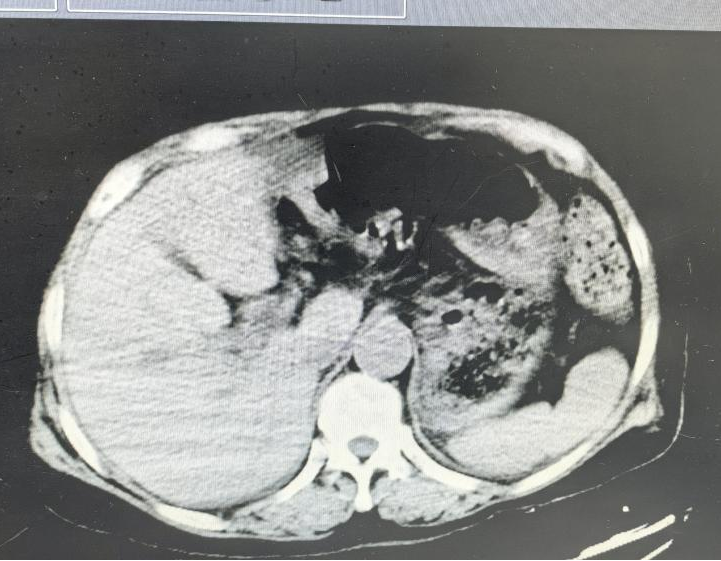

术后复查CT

让人欣慰的是,奉老太恢复得比预想快得多。科室全面推行的ERAS加速康复方案起了作用:术后尽早下床、尽早进食、优化镇痛,让患者少遭罪、早出院。

出院那天,家属发来一面电子锦旗:“医德高尚,医术精湛;精心护理,热情周到!”